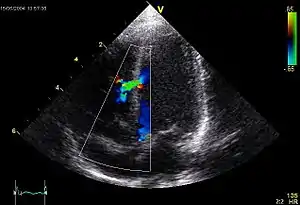

![]() An abnormal echocardiogram: Image shows a midmuscular ventricular septal defect. The trace in the lower left shows the cardiac cycle and the red mark the time in the cardiac cycle when the image was captured. Colors are used to represent the velocity and direction of blood flow. | |

Echocardiography can help detect cardiomyopathies, such as hypertrophic cardiomyopathy, dilated cardiomyopathy, and many others. The use of stress echocardiography may also help determine whether any chest pain or associated symptoms are related to heart disease. The biggest advantage of echocardiography is that it is not invasive (does not involve breaking the skin or entering body cavities) and has no known risks or side effects.[4] Not only can an echocardiogram create ultrasound images of heart structures, but it can also produce accurate assessment of the blood flowing through the heart by Doppler echocardiography, using pulsed- or continuous-wave Doppler ultrasound. This allows assessment of both normal and abnormal blood flow through the heart. Color Doppler, as well as spectral Doppler, is used to visualize any abnormal communications between the left and right sides of the heart, any leaking of blood through the valves (valvular regurgitation), and estimate how well the valves open (or do not open in the case of valvular stenosis). The Doppler technique can also be used for tissue motion and velocity measurement, by tissue Doppler echocardiography.